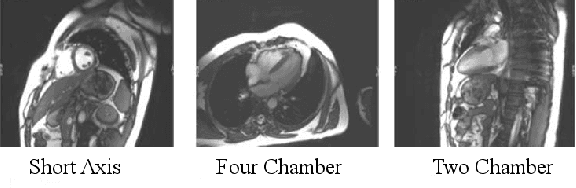

We consider the problem of automatically prescribing oblique planes (short axis, 4 chamber and 2 chamber views) in Cardiac Magnetic Resonance Imaging (MRI). A concern with technologist-driven acquisitions of these planes is the quality and time taken for the total examination. We propose an automated solution incorporating anatomical features external to the cardiac region. The solution uses support vector machine regression models wherein complexity and feature selection are optimized using multi-objective genetic algorithms. Additionally, we examine the robustness of our approach by training our models on images with additive Rician-Gaussian mixtures at varying Signal to Noise (SNR) levels. Our approach has shown promising results, with an angular deviation of less than 15 degrees on 90% cases across oblique planes, measured in terms of average 6-fold cross validation performance -- this is generally within acceptable bounds of variation as specified by clinicians.